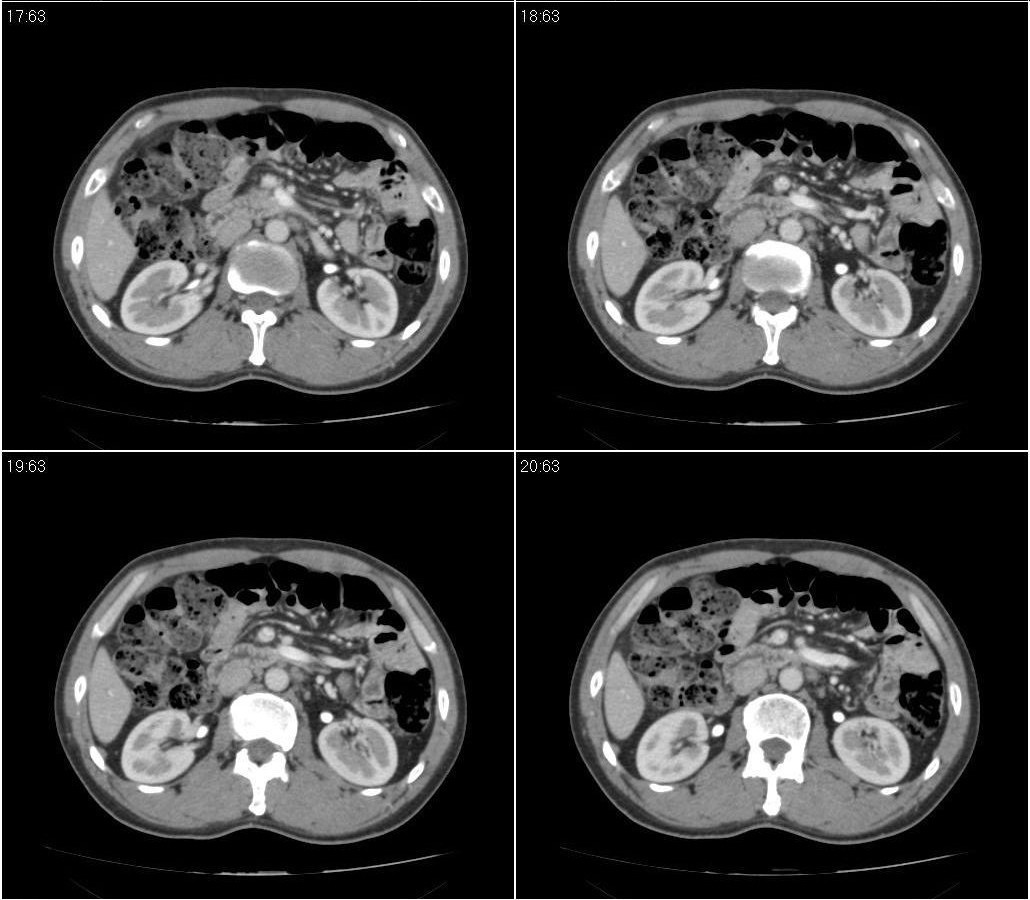

标题: CT21384:男性,50岁。发现无痛性黄疸十余天,B朝提示肝胆管 [打印本页]

标题: CT21384:男性,50岁。发现无痛性黄疸十余天,B朝提示肝胆管

1.考虑:壶腹占位病变(癌?)。

2.胆系低位梗阻:肝内外胆管扩张,胆囊增大,胰管扩张。

胰头癌伴低位胆道梗阻。

胆系低位梗阻(肝内外胆管扩张,胆囊增大,胰管扩张);考虑胰头癌或壶腹癌所致。

胆总管突然中断,壁增厚且强化,考虑胆总管癌可能性大伴胆系梗阻,胆囊炎

胰头强化欠均匀,胆胰管扩张。考虑胰头癌可能性大。

胆系低位梗阻(肝内外胆管扩张,胆囊增大,胰管扩张,钩突似有占位);考虑胰头癌